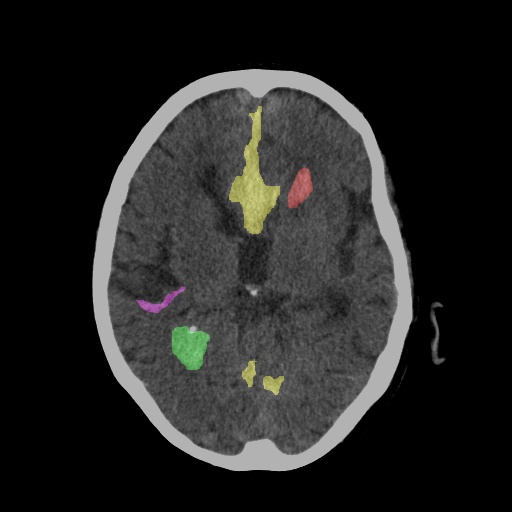

CT Scan After Diagnosis with Segmentation

Detection

Detection & Tracking

Identifies and tracks the location and progression of hemorrhage lesions across multiple scans over time.